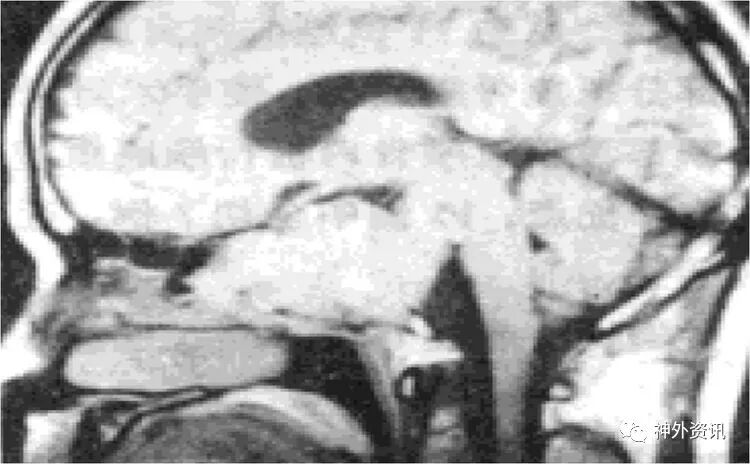

图1-5(含篇首),来自Rhoton教授《The Foramen Magnum》